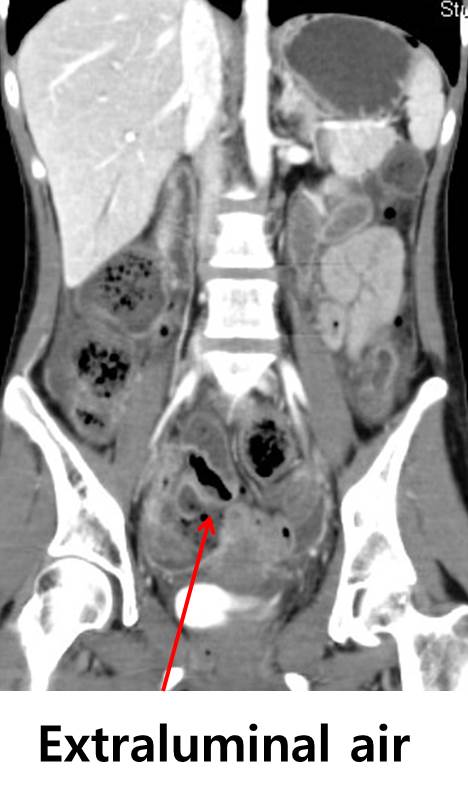

[Polyarteritis nodosa (PAN) with small bowel perforation]